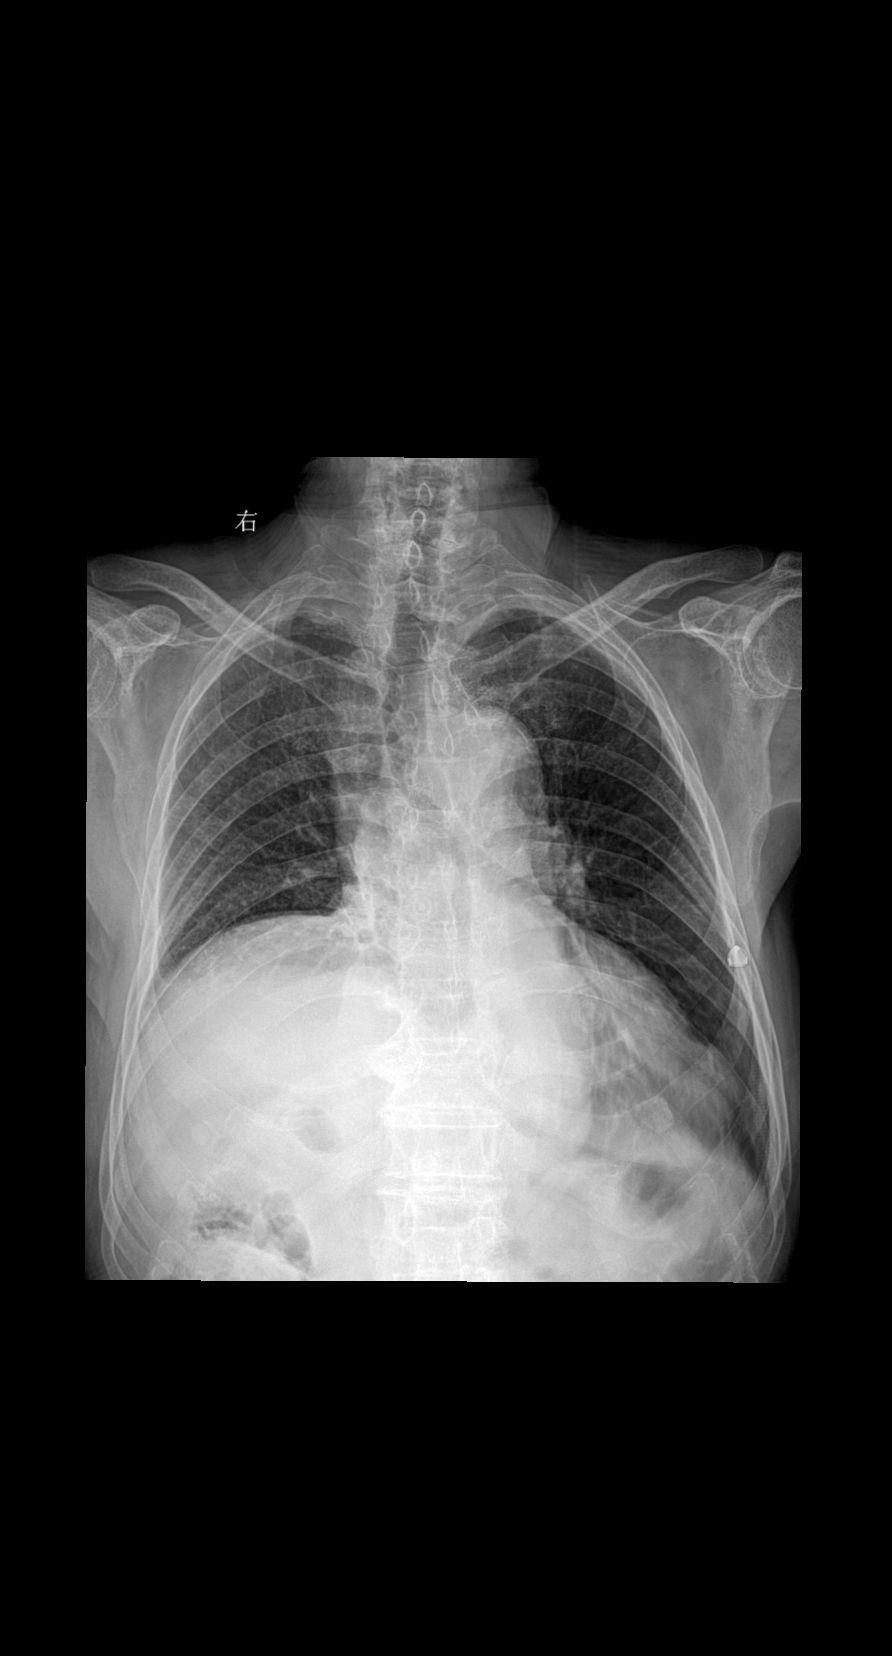

主诉:咳嗽 闷气 男 80y 考虑什么家人们?答案打到评论区

2025-02-25 16:12